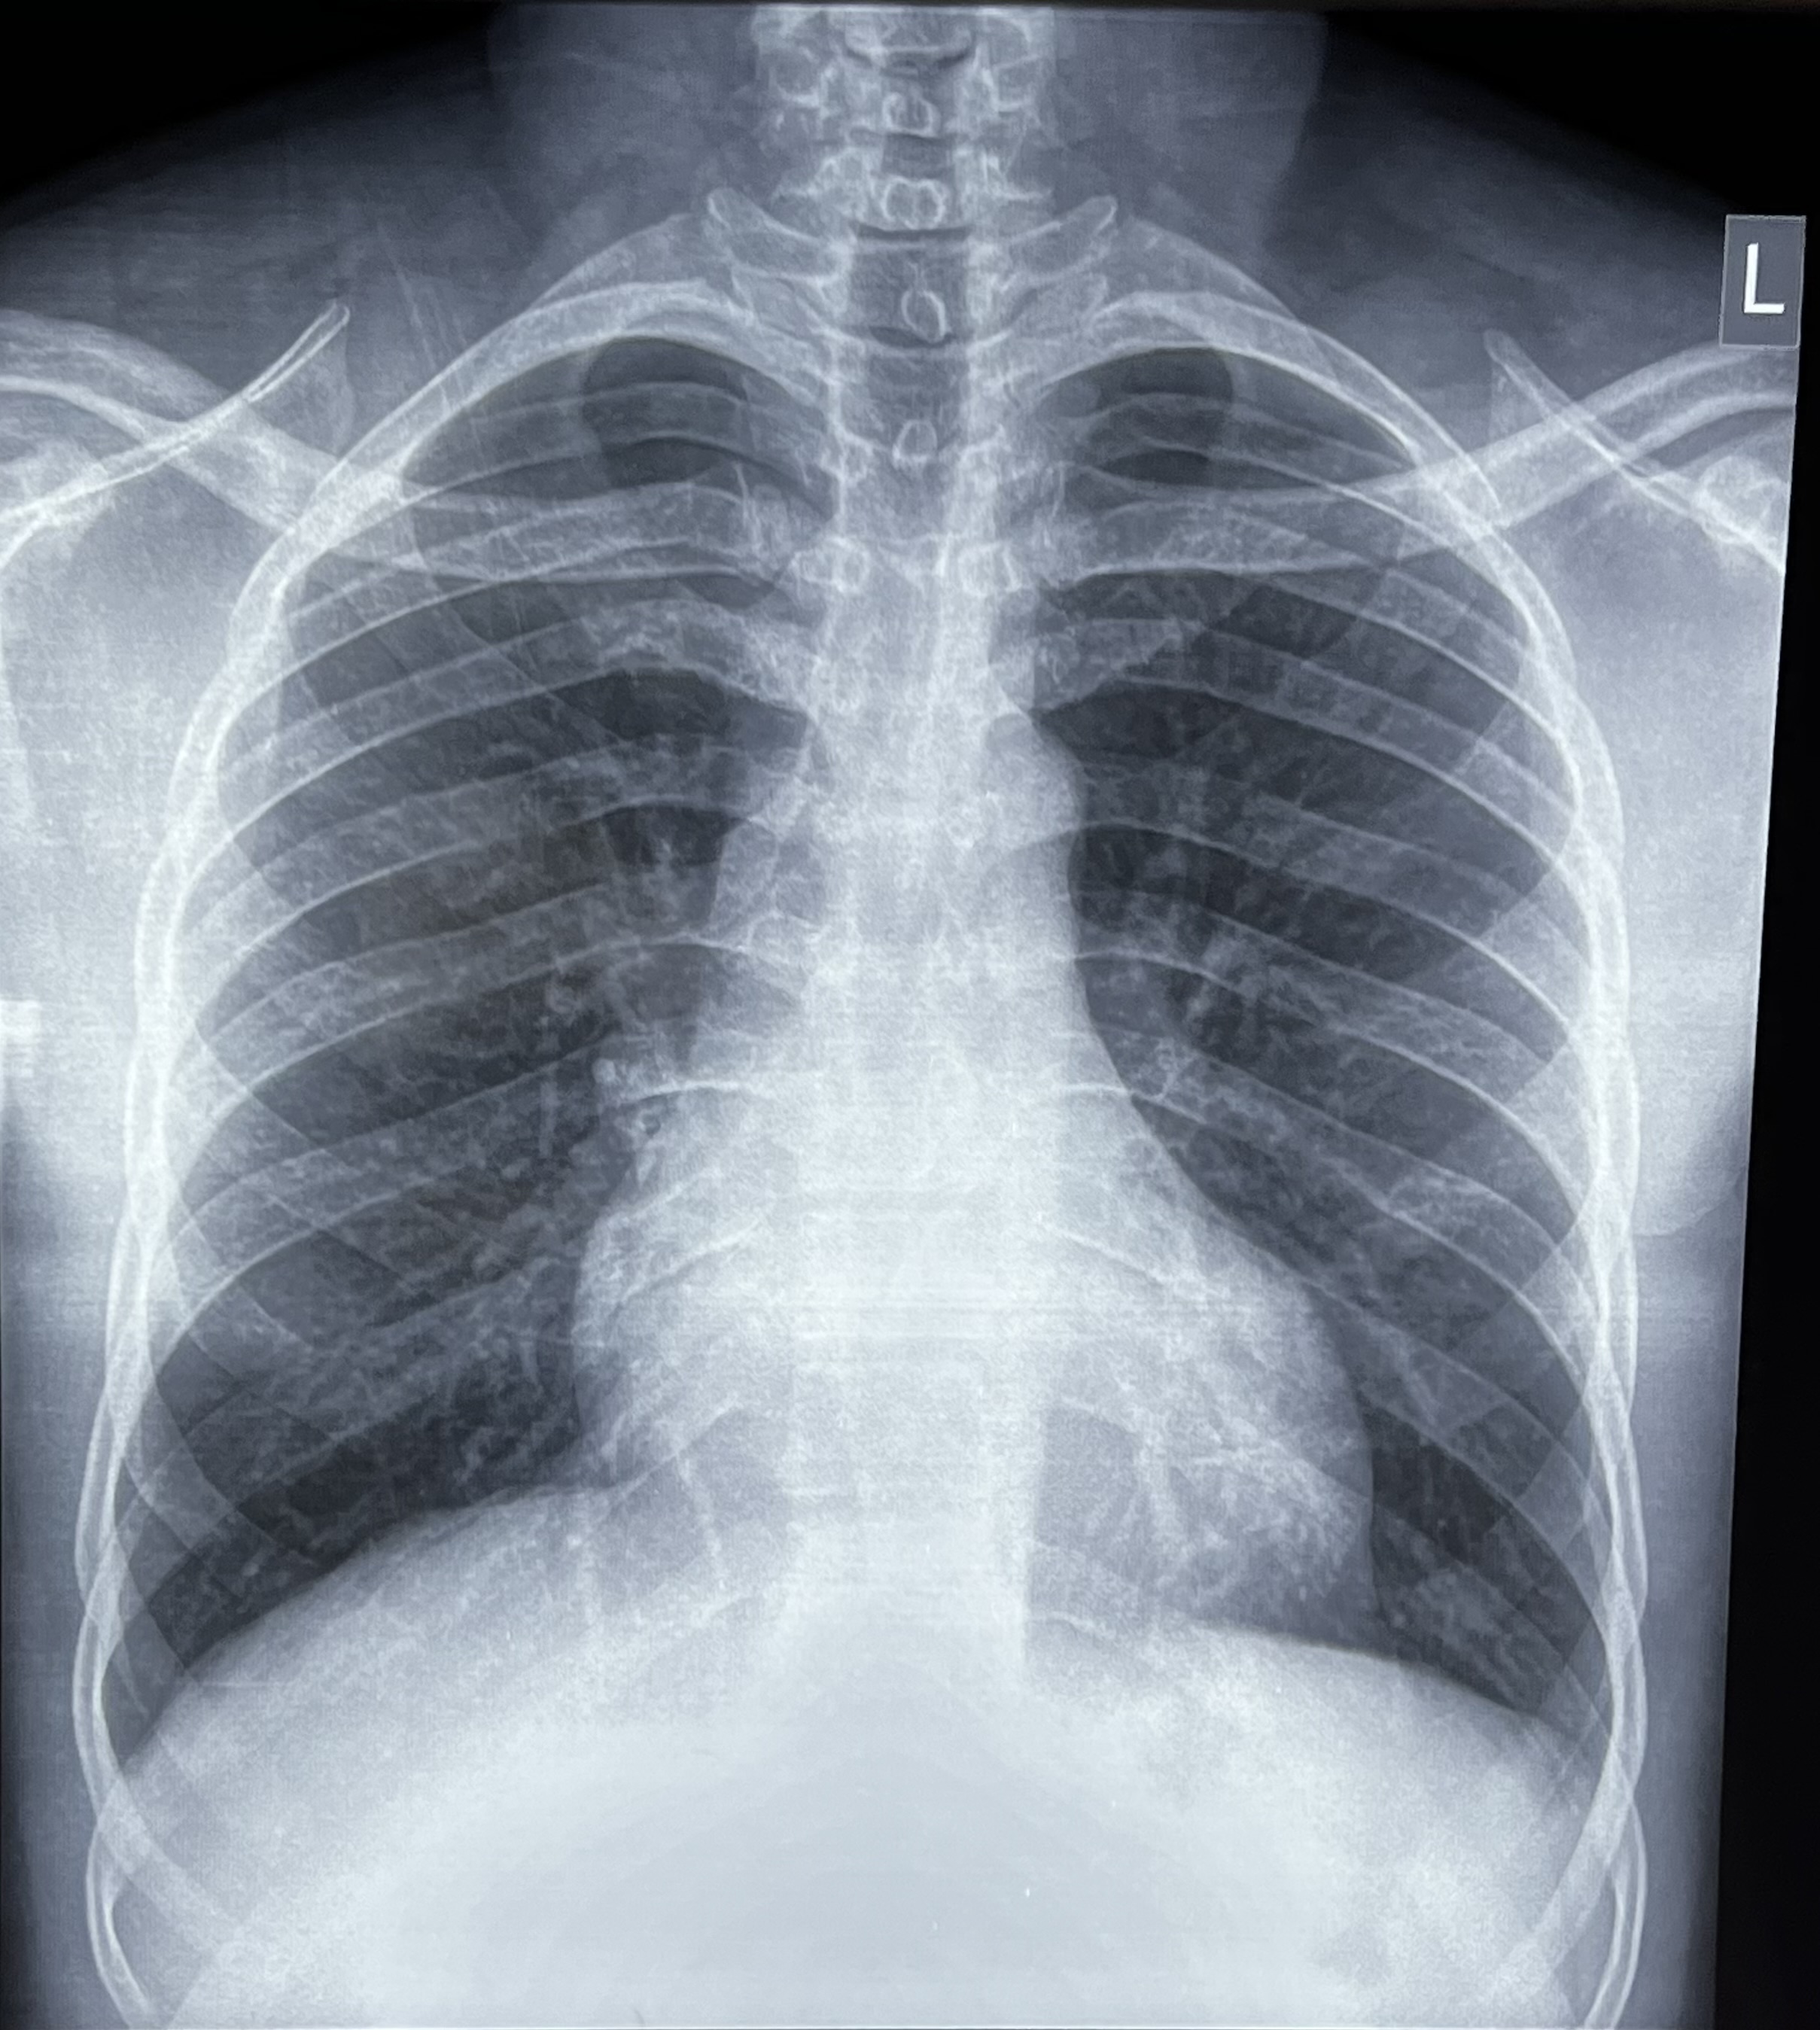

Radiology